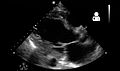

Ultrasound

Echocardiography is commonly used to support a clinical diagnosis of heart failure. This modality uses ultrasound to determine the stroke volume (SV, the amount of blood in the heart that exits the ventricles with each beat), the end-diastolic volume (EDV, the total amount of blood at the end of diastole), and the SV in proportion to the EDV, a value known as the ejection fraction (EF). In pediatrics, the shortening fraction is the preferred measure of systolic function. Normally, the EF should be between 50 and 70%; in systolic heart failure, it drops below 40%. Echocardiography can also identify valvular heart disease and assess the state of the pericardium (the connective tissue sac surrounding the heart). Echocardiography may also aid in deciding what treatments will help the person, such as medication, insertion of an implantable cardioverter-defibrillator, or cardiac resynchronization therapy. Echocardiography can also help determine if acute myocardial ischemia is the precipitating cause, and may manifest as regional wall motion abnormalities on echo.